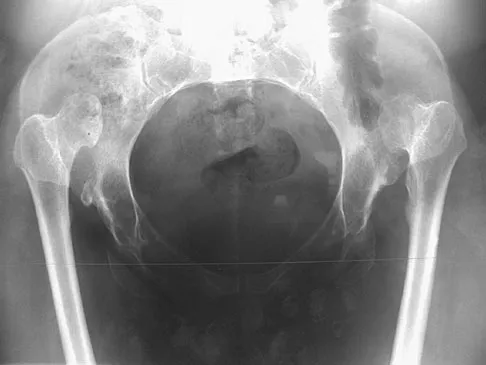

A 62-year-old woman reports diffuse aches and pains of the hip and pelvis. She denies any significant trauma but does have a history of chronic anemia. Figure 17a shows a radiograph of the pelvis, and Figures 17b and 17c show T2-weighted MRI scans. What is the most likely diagnosis?

Explanation